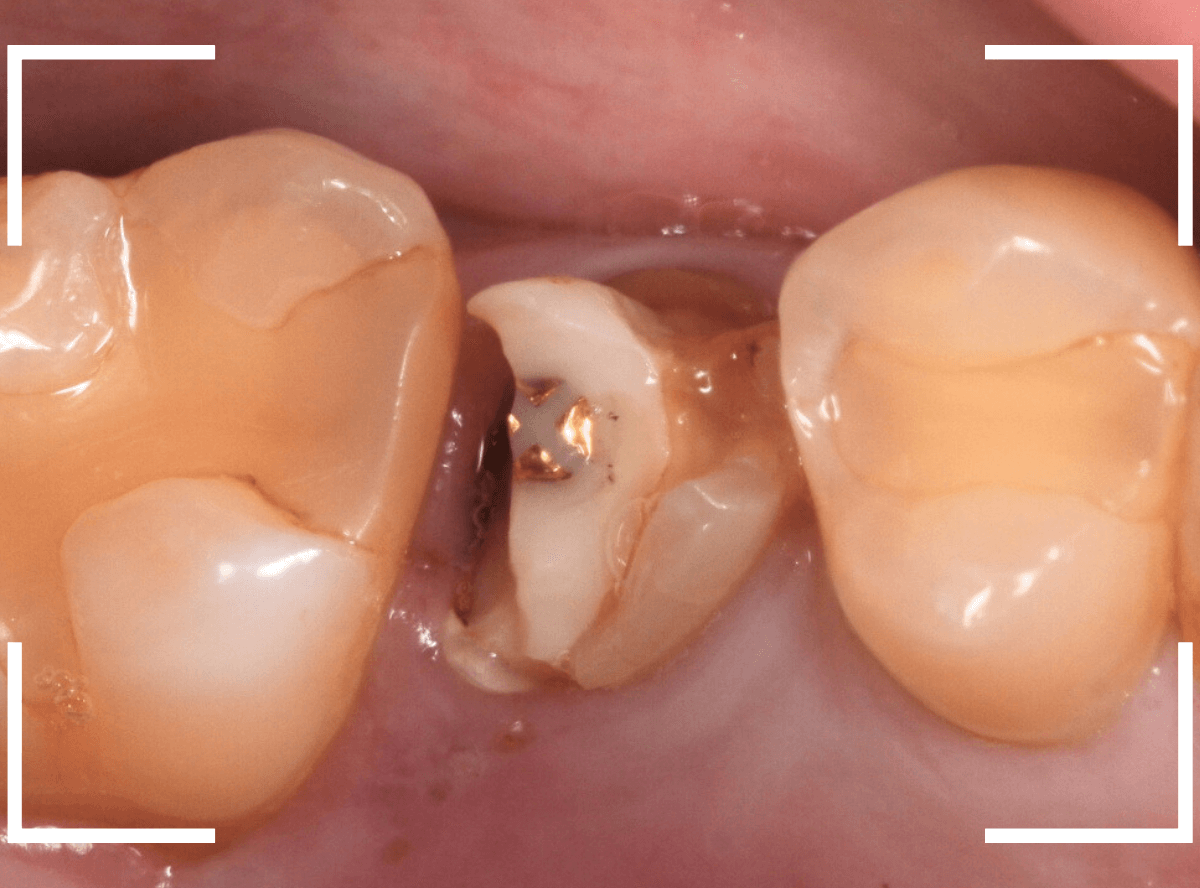

Case.10

さし歯を入れるスペースがない!

一番奥の歯が土台(コア)の治療までで中断してしまってる患者さんの例です。

本来であれば、この上にさし歯を作らなければいけないのですが、この時点でかみ合ってしまい、さし歯を作ろうにも作りづらい状況でうやむやのうちに治療中断になってしまったようです。

まず、土台の治療をしてから時間が経過していることと、不適合になっている事から、外して中を調べます。

すると、土台の中で虫歯にもなっていました。

(〇部の赤い部分)

こういった事は、レントゲン写真でもよくわからない事が多く、土台を外す治療は本当に神経を使います。

今回は、歯肉の中まで歯が欠損しているので、このまま土台とさし歯を作り直しても、いい結果にはなりません。

患者さんに状況を説明し、歯の周りの歯肉を麻酔をして電気メスでトリミングします。

このように歯の際が歯肉からしっかり出てる状況で製作しないと、さし歯はしっかりお口の中で安定しません。